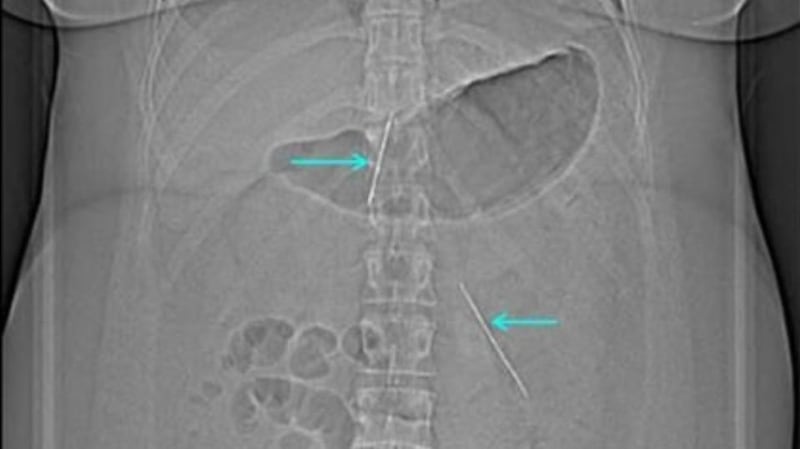

The patient attended the emergency department reporting that she had a single needle lodged in her chest, but a subsequent X-ray detected at least 19 foreign objects in her body.

A needle that was penetrating the right ventricle of the patient’s heart was removed, along with two needles that had been lodged in her abdomen. The operation was completed without complication.